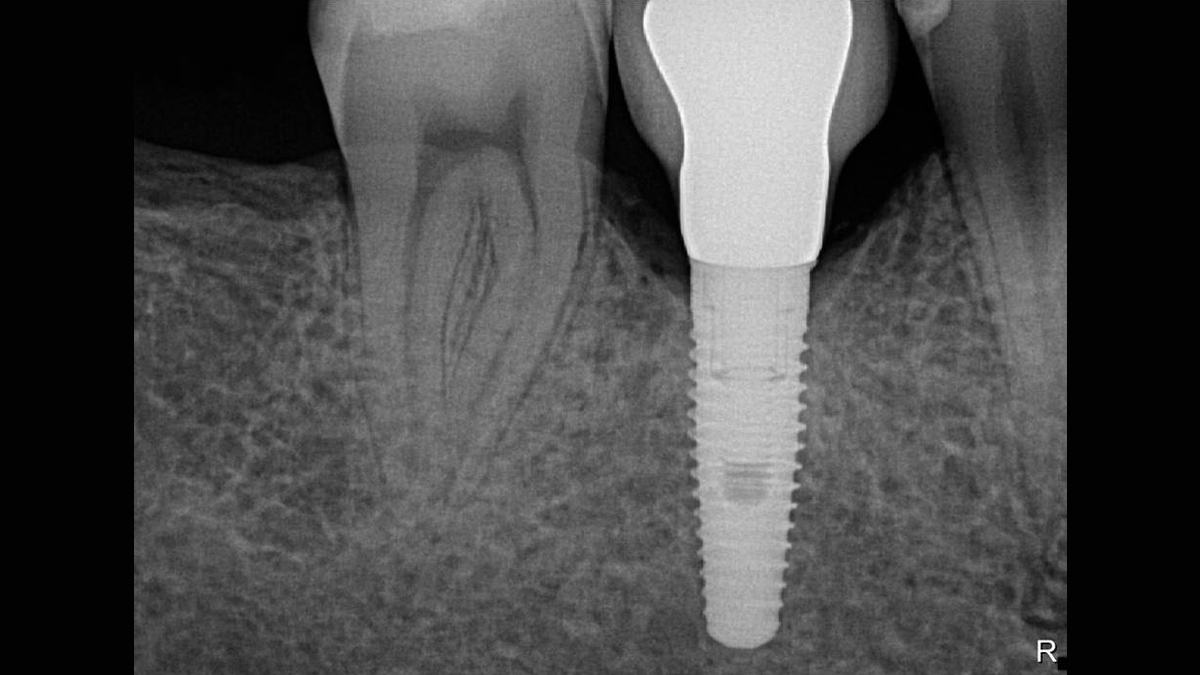

Excellent Image Quality

Schick 33 provides a theoretical resolution of 33 lp/mm and a 15 μm pixel size delivering superb image quality without the additional wait time caused by a developing or scanning process.

With Schick 33 sensors you have the option of five different filtering options: General Dentistry, Endodontics, Periodontics, Restorative and Hygiene. These clinically specific views are designed to optimize your diagnosis, enhancing the image to suit your needs.

Schick 33 - Gallery of Sample Images